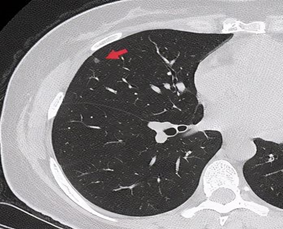

实性微结节—低危

99%良性